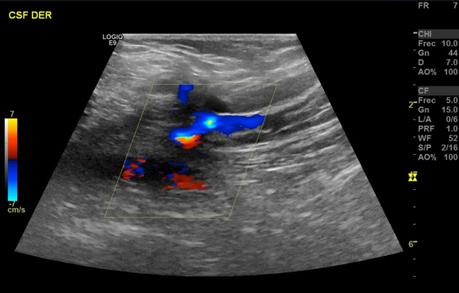

Se realizaron múltiples barridos ecográficos con transductor lineal de 9 MHz en escala de grises, Doppler color y espectral, con paciente en decúbito supino, efectuando valoración del sistema venoso superficial y profundo, observando siguientes hallazgos:

El sistema venoso superficial se observa con presencia de reflujo a la aplicación doppler a nivel de la vena safena mayor y vena safena menor.

• INSUFICIENCIA VENOSA SUPERFICIAL DE VENA SAFENA MAYOR Y VENA SAFENA MENOR, CON ALGUNAS VENAS ACCESORIAS EN TERCIO INFERIOR DE LA PIERNA.